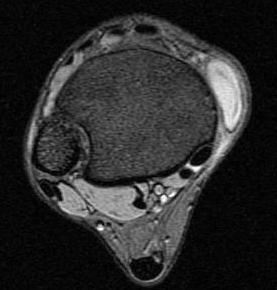

GCT flexor tendon sheath

GCT of tibialis posterior tendon sheath